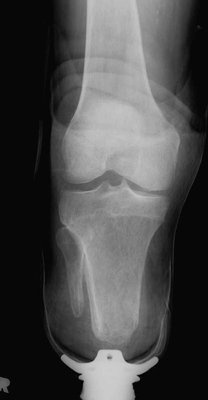

Immediate post-operative films of a good BKA. Stump-shrinking cast and skin staples